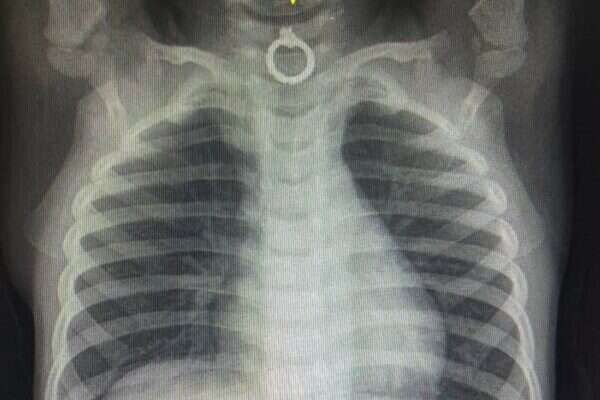

הצוות הרפואי ביצע בדחיפות צילום רנטגן וגילה כי הפעוט בלע עגיל טבעת מוזהב דק, שהתמקם באזור המסוכן בכניסה לוושט, בסמוך לקנה הנשימה.

בשל המיקום המסוכן של הגוף הזר, הובהל הפעוט בדחיפות לחדר הניתוח על ידי רופאי מחלקת אף אוזן גרון ד"ר סער אוחיון וד"ר מרואן כרם, ובאמצעות ציוד אופטי חדיש העגיל חולץ בהצלחה מגרונו.